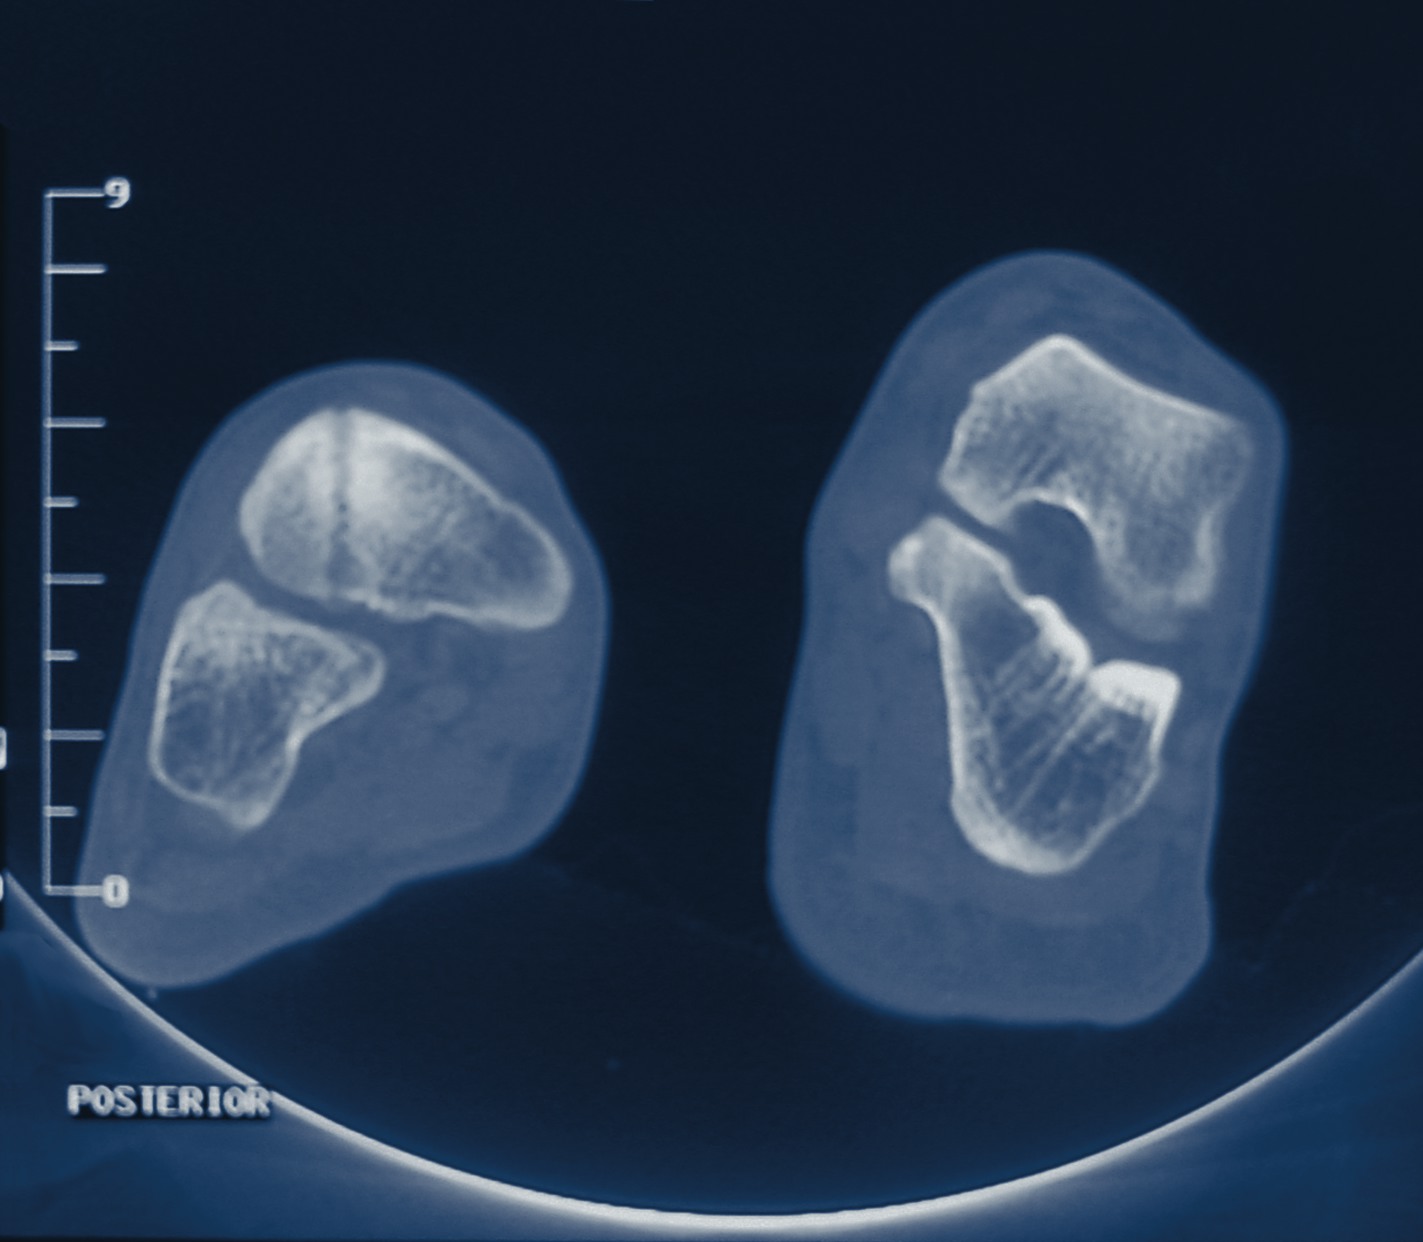

Physicians reportedly obtain over 60 million computed tomography (CT) scans each year in the United States. However, a recent study in the New England Journal of Medicine (NEJM) suggests that CT scans may be linked to an increased risk of radiation exposure and cancer. Citing evidence from epidemiologic studies, the authors of the NEJM article indicate that organ doses from a common CT study, consisting of two or three scans, may result in an increased risk of cancer. “As compared with plain film radiography, CT involves much higher doses of radiation, resulting in a marked increase in radiation exposure in the population,” note the authors of the NEJM review article. They concede that there are no currently published epidemiologic studies that look at cancer risks associated with CT scans. However, the authors of the NEJM article note that “applying organ-specific cancer incidence or mortality data” from long-term follow-up studies of atomic bomb survivors allows estimates of the link between radiation exposure from CT scans and cancer risk. Citing reports from the literature, the authors of the NEJM review suggest that CT scans are overutilized and may be part of a defensive medicine approach. Robert Baron, DPM, echoes the study’s concern about defensive medicine. “Unfortunately, this has developed largely due to our litigious society,” says Dr. Baron, a Professor and Chairman of the Department of Radiology at William M. Scholl College of Podiatric Medicine at Rosalind Franklin University. “These exams are also ordered without much regard to the radiation exposure received by patients. Exposure can be minimized with proper workup and scanning limited to a very specific area.” Daniel Evans, DPM, says there is “no question” that ionizing radiation can lead to cell changes, which may precipitate the development of cancer. However, no longitudinal study has demonstrated a direct connection between CT exposure and the development of cancer, and he notes that the NEJM review extrapolated gamma radiation from Hiroshima and Nagasaki to other types of radiation such as X-ray. “The level and extent of the biological effects may vary,” says Dr. Evans. Dr. Evans, the Assistant Chairman of the Department of Radiology at the William M. Scholl College of Podiatric Medicine, also points out that the NEJM review looked at CT scans done on the abdomen and chest, which would give more ionizing radiation to internal organs, lymphatic tissue and gonadal tissue. There is no data specific to the lower extremity. Podiatrists most commonly use CT scans for conditions such as Lisfranc fractures, calcaneal fractures, coalitions, suspected osteomyelitis, Charcot neuroarthropathy and ankle fractures, according to Drs. Evans and Baron. Dr. Evans notes that podiatric scans are performed in areas that have a low incidence for the development of cancer. He says podiatric studies are rarely done repeatedly on the same patient, which minimizes the cumulative dosing to patients.